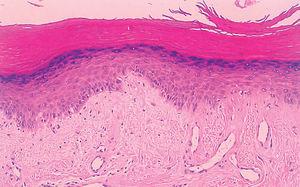

La biopsia de una pápula de los nudillos reveló la existencia de hiperqueratosis y acantosis, junto con edema en dermis superficial, dilatación vascular y abundantes melanófagos. En la capa basal se observaban mínimos focos de vacuolización con queratinocitos necróticos aislados (fig. 3). Las analíticas mostraron unas enzimas musculares (creatincinasa [CK], su enzima miocárdica [CK-MB] y aldolasa) y transaminasa glutamiooxalacética en rangos de normalidad. El estudio de autoinmunidad únicamente fue positivo para los ANA, con valores de 1/1.280 y patrón moteado en HEP-2. Los anti-ADN, anti-Ro, anti-La, anti-RNP, anti-Sm y anti-Jo1 fueron negativos.

Fig. 3.--Hiperqueratosis, acantosis y vacuolización de la membrana basal, con leve infiltrado linfohistocitario perivascular superficial. (Hematoxilina-eosina, x100.)